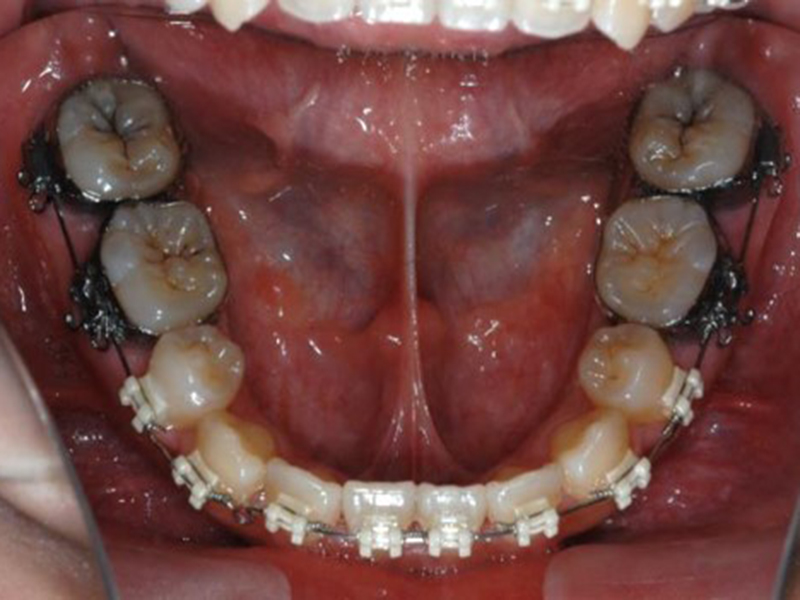

▼ ケース5 下顎前歯部叢生症例

初診時X線写真